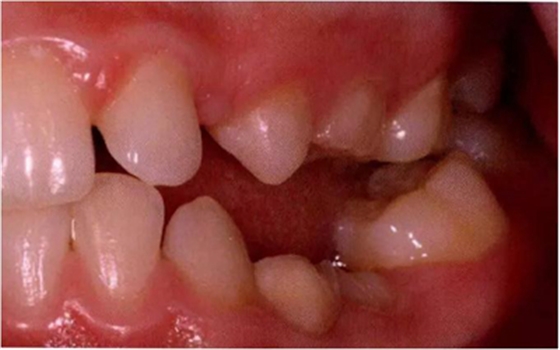

圖8展示了一張5歲孩子右下第二乳磨牙嚴(yán)重下沉的口內(nèi)像。臨床檢查可見(jiàn)右下第一乳磨牙遠(yuǎn)中傾斜,朝向下沉乳牙。X線片檢查顯示所有恒牙胚都存在(圖9)。無(wú)論是臨床還是影像學(xué),都可檢查到有齲齒的存在。鑒于這顆下沉乳牙在年齡較小時(shí)就已經(jīng)非常嚴(yán)重,同時(shí)還患有齲病,因此決定予以拔除。后期在放置間隙保持器的同時(shí)還應(yīng)持續(xù)觀察監(jiān)測(cè)右下第一恒磨牙和第二前磨牙的萌出情況。

圖8:一名五歲患兒右側(cè)下頜第二乳磨牙嚴(yán)重下沉臨床像